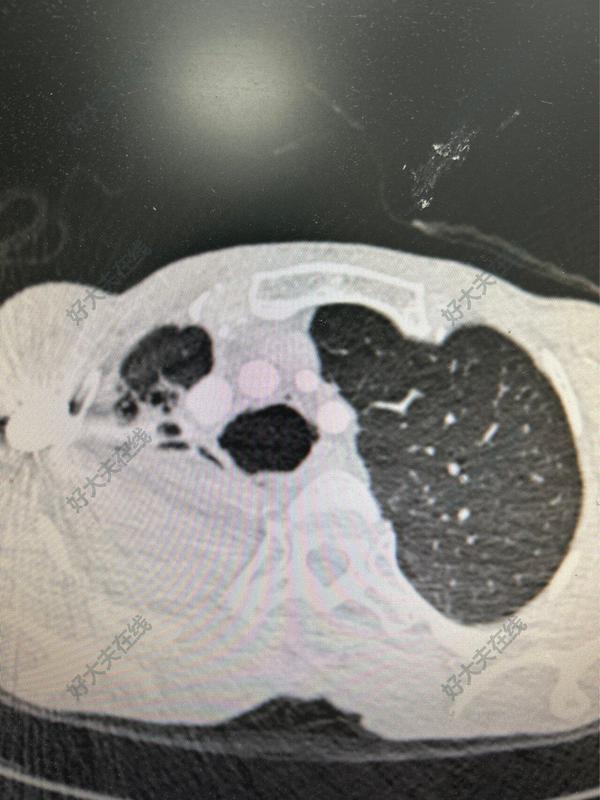

治疗前患者曲霉菌肺炎2024.5月因抗真菌治疗后肝功能异常,停药。于2024.10再次出现咯血收入内科。期间间断大咯血,单次咯血量100ml。我科会诊后考虑侵袭性肺曲霉菌病右上肺病灶侵蚀血管出现咯血,手术是根治咯血的最佳办法。但未规范抗真菌,术后并发症多。且胸摸顶粘连分离过程中滋养血管多术中出血多。故建议先行介入预栓塞止血并内科规范抗真菌至少一月后再择期手术。介入科2天后行栓塞止血,效果不佳,仍咯血。为抢救生命急诊行手术切除右上肺。术前充足备血。治疗中术中钝性➕锐性慢慢分离粘连,避免损伤大血管且避免切破右上肺病灶导致胸腔内感染。分离过程中及分离后创面大量渗血,纱布加压止血。分离完粘连后,右肺叶裂融合,选择单向式切除右上肺。分离粘连2小时,切肺1小时,止血关胸4小时,总耗时约8小时。术中输血红细胞6U,血浆400ml。因急诊未能评估气管黏膜情况且患者未规范抗真菌,故子女宫支气管残端包埋。因胸腔内广泛粘连,纵隔胸膜及心包前脂肪均不能包埋,遂游离前纵隔胸膜连通胸腺组织行支气管残端包埋。治疗后治疗后7天普通病房继续抗真菌,抗感染,呼吸道管理,患者逐步恢复,未再咯血。复查胸部CT右下肺较前复张。逐步拔管后恢复口服抗真菌治疗。计划近期出院。治疗后即刻术后引流管渗血明显,即刻入ICU治疗,继续给予输血,输凝血因子,抗休克治疗。2天后患者渗血逐步减少,复查胸部CT右下肺实变,即行纤支镜吸痰,患者病情逐步稳定后术后第2天转普通病房。